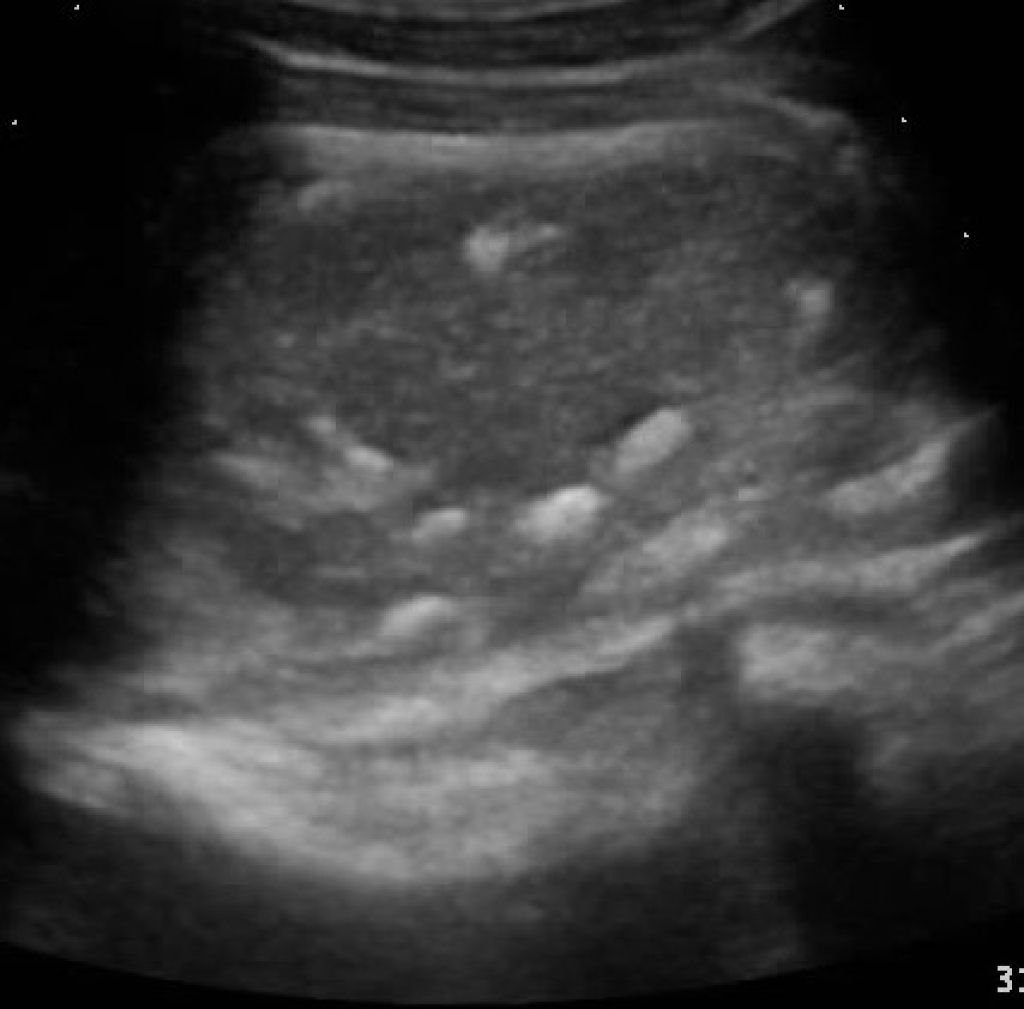

De klinische klachten van een paard met een slijmbeursontsteking in de hals tonen veel gelijkenis met mogelijke klachten bij andere halsproblemen. De zwelling boven de eerste twee halswervels is echter wel vrij typerend voor een bursitis van de bursa subligamentosa. De diagnose kan pas echt hard gemaakt worden aan de hand van een echo van het voorste gedeelte van de hals. Op de echo zal een ontstoken slijmbeurs duidelijk opgezwollen zijn ten opzichte van normaal. Ook kunnen röntgenopnamen vaak helpen, aangezien er vaak verkalkingen in de bursa te zien zijn.

Links: Overvulling en verkalkingen van de slijmbeurs van de nekband

Rechts: Echobeeld: slijmbeursontsteking met mineralisaties

Een slijmbeurs is gevuld met synovia, dezelfde smerende vloeistof die we ook in gewrichten vinden. Bij normale slijmbeurzen zijn deze zeer weinig gevuld en bijna niet zichtbaar. Net zoals bij gewrichtsproblemen is de slijmbeurs bij een slijmbeursontsteking echter overvuld met synovia als gevolg van de chronische irritatie. Vaak zijn er hierin ook mineralisaties (kalkdeeltjes) te zien. Een slijmbeursontsteking kan behandeld worden door het teveel aan synovia af te laten vloeien en de slijmbeurs in te spuiten met ontstekingsremmers. Helaas zien we in de praktijk met enige regelmaat dat de slijmbeursontsteking na verloop van tijd weer terugkomt. Als het inspuiten van de slijmbeurs met ontstekingsremmers onvoldoende werkt kan het een oplossing zijn om de slijmbeurs met een kijkoperatie uit te ruimen en op te schonen (of geheel te verwijderen).